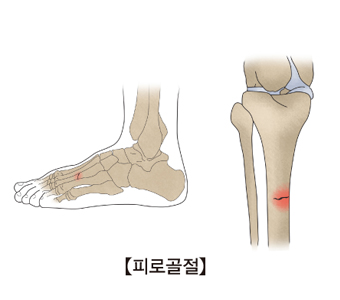

평상시 잘 사용하지 않던 몸을 사납게 사용하는 경우, 작은 바깥쪽 충격에도 뼈가 부러지는 등 골절을 겪기 쉬운 상태가 되요. 골절은 아무리 미세하고 약한 정도라도, 일상생활에 부담을 주고요.